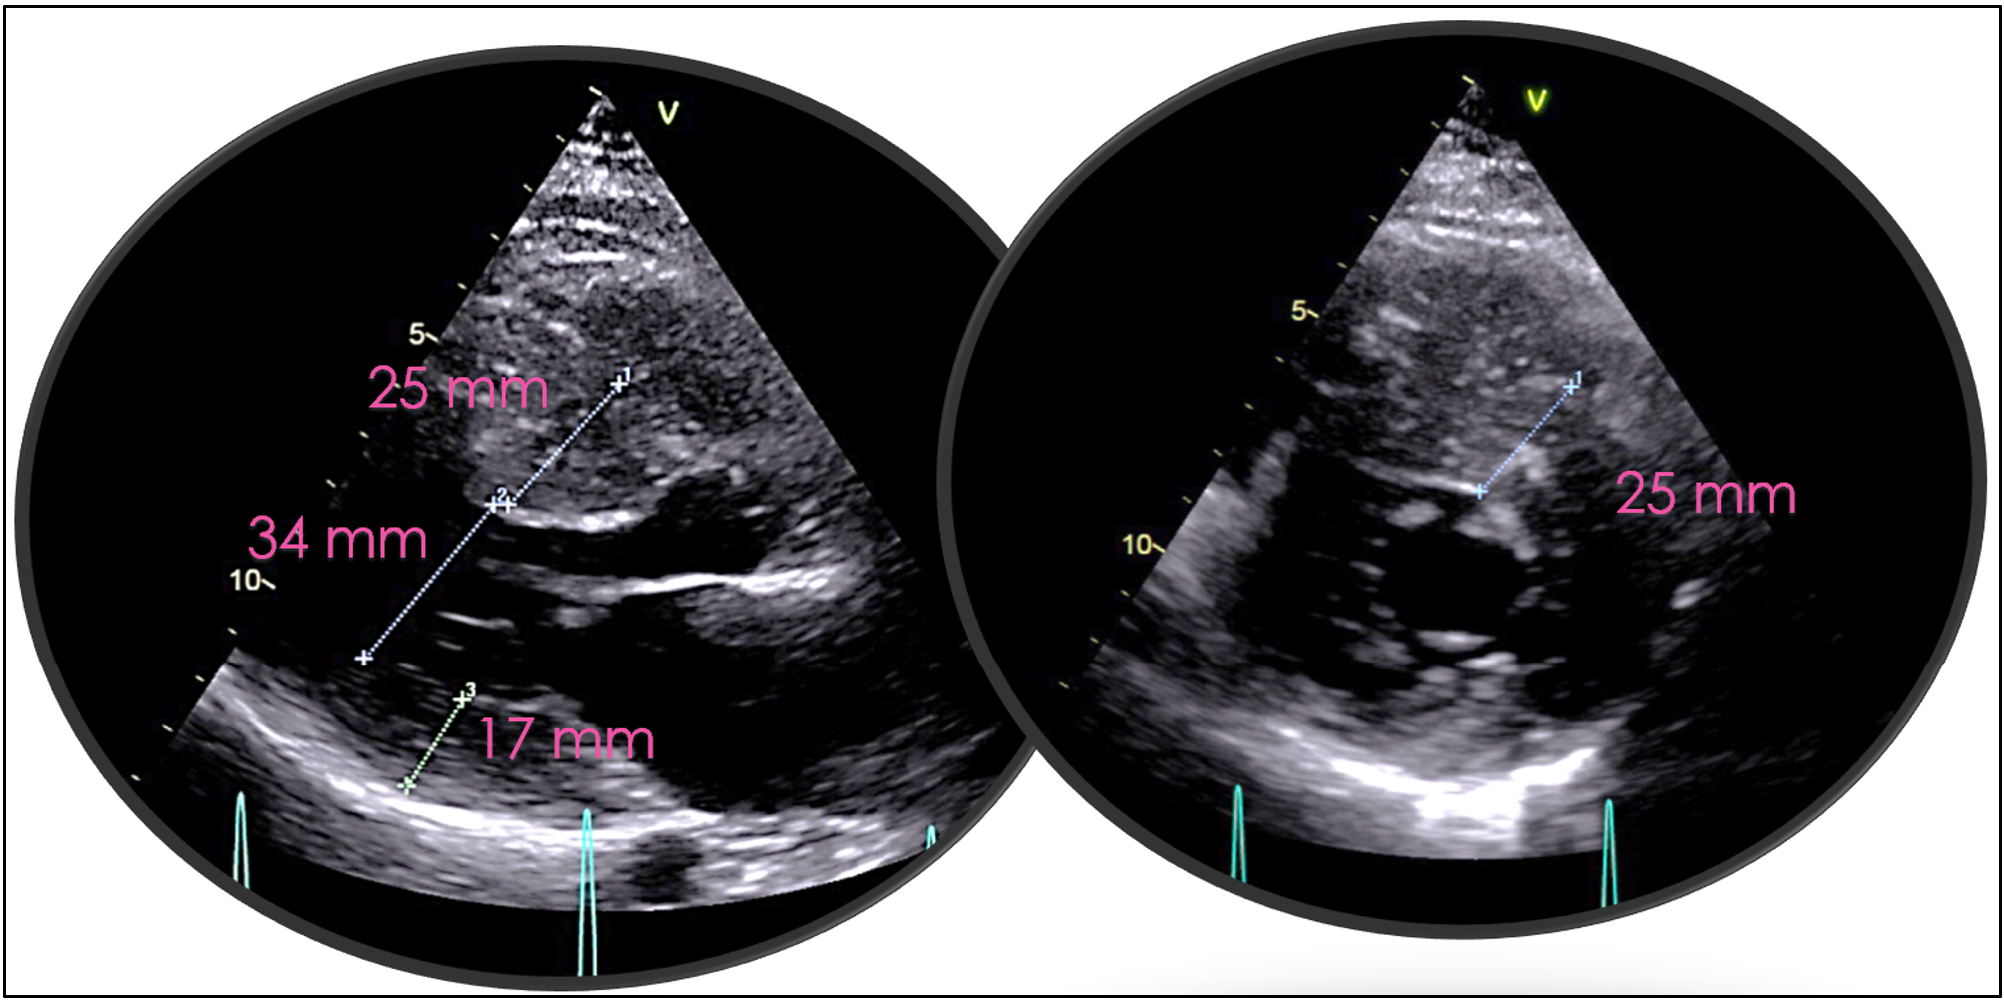

Introduction Hypertrophic cardiomyopathy (HCM) is a genetically heterogeneous myocardial disease characterized by marked phenotypic variability, even among carriers of the same pathogenic mutation. Pregnancy in women with obstructive HCM represents a high-risk condition, particularly in the presence of severe left ventricular outflow tract (LVOT) obstruction and limited pharmacological options. We report a case highlighting the challenges of risk stratification and management of obstructive HCM during pregnancy. Case Presentation A 24-year-old woman with a family history of HCM was referred for cardiological evaluation during the third month of pregnancy. Genetic testing identified a pathogenic MYH7 variant (c.1987C>T, exon 18), shared with her mother and sister. Marked intrafamilial phenotypic variability was observed, with both obstructive and non-obstructive HCM phenotypes; the patient’s mother and grandmother were obstructive, whereas her sister was non-obstructive, and the patient showed cardiac involvement from the neonatal period. At presentation, she reported dyspnea on mild-to-moderate exertion (NYHA class III). Electrocardiography showed left atrial enlargement and left ventricular hypertrophy with secondary right ventricular repolarization abnormalities (Fig. 1). Transthoracic echocardiography revealed severe concentric hypertrophy (septal thickness 25 mm), grade II diastolic dysfunction, systolic anterior motion of the mitral valve, and severe LVOT obstruction with a peak gradient >150 mmHg (Fig. 2). Due to the high maternal risk and limited pharmacological options during pregnancy, close outpatient monitoring was adopted. Given an estimated HCM sudden cardiac death risk of 6.62%, a subcutaneous implantable cardioverter-defibrillator was implanted during pregnancy. The patient completed pregnancy without major complications and delivered at term by elective cesarean section. Postpartum optimization of medical therapy led to symptomatic improvement (NYHA II). Subsequently, CYP2C19 genotyping was performed to evaluate potential eligibility for treatment with the cardiac myosin inhibitor mavacamten. Conclusion This case underscores the complexity of managing obstructive HCM during pregnancy, emphasizing the importance of early risk assessment, multidisciplinary care, and individualized management strategies, particularly in patients with severe LVOT obstruction and significant intrafamilial phenotypic variability.